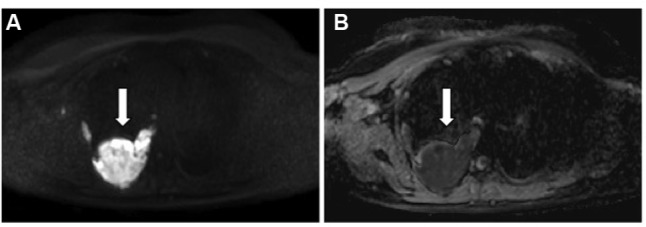

恶性胸膜间皮瘤(MPM)是一种治疗选择有限的疾病,其管理仍然存在争议。通常通过胸腔镜进行诊断,允许多次活检并进行组织学分型,并用于外科候选人的分期目的。国际间皮瘤兴趣小组和国际肺癌研究协会建立的TNM分期系统是临床使用的推荐和最近更新的分类,该系统主要基于手术和病理变量以及横断面成像。对比增强计算机断层扫描是主要的成像程序。目前,最常用的MPM测量系统是改进的实体肿瘤反应评价标准(RECIST)方法,该方法基于垂直于胸壁或纵隔的肿瘤厚度的一维测量。磁共振成像和18f -氟-2-脱氧-d -葡萄糖正电子发射断层扫描的功能成像可以提供额外的分期信息在选择的情况下,尽管这种方法的有用性是有限的患者接受胸膜切除术。MPM的分子重分类和基因表达或miRNA预后模型有可能改善预后和患者选择适当的治疗算法;然而,他们等待在临床实践中引入前瞻性验证。

Malignant pleural mesothelioma (MPM) is a disease with limited therapeutic options, the management of which is still controversial. Diagnosis is usually made by thoracoscopy, which allows multiple biopsies with histological subtyping and is indicated for staging purposes in surgical candidates. The recommended and recently updated classification for clinical use is the TNM staging system established by the International Mesothelioma Interest Group and the International Association for the Study of Lung Cancer, which is based mainly on surgical and pathological variables, as well as on cross-sectional imaging. Contrast-enhanced computed tomography is the primary imaging procedure. Currently, the most used measurement system for MPM is the modified Response Evaluation Criteria in Solid Tumors (RECIST) method, which is based on unidimensional measurements of tumor thickness perpendicular to the chest wall or mediastinum. Magnetic resonance imaging and functional imaging with 18F-fluoro-2-deoxy-D-glucose positron-emission tomography can provide additional staging information in selected cases, although the usefulness of this method is limited in patients undergoing pleurodesis. Molecular reclassification of MPM and gene expression or miRNA prognostic models have the potential to improve prognostication and patient selection for a proper treatment algorithm; however, they await prospective validation to be introduced in clinical practice.